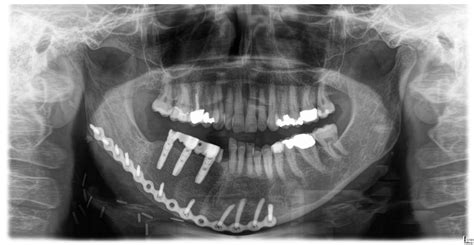

The Albert Fish X Ray is a cutting-edge imaging technology designed to provide detailed internal views of the human body. Named after the infamous serial killer Albert Fish, this technology has been developed to assist in the identification and analysis of human remains, particularly in cases where traditional methods fall short. The Albert Fish X Ray uses high-energy X-rays to penetrate deep into tissues, bones, and other structures, revealing hidden details that would otherwise go unnoticed.

• Identification of Human Remains: The Albert Fish X Ray can help identify human remains by providing detailed images of bones and other internal structures. This is particularly useful in cases where the remains are decomposed or fragmented.

• Detection of Trauma and Injuries: The technology can detect fractures, gunshot wounds, and other forms of trauma that may not be visible to the naked eye. This information is crucial for reconstructing the events leading up to a person's death.

• albert fish needles x ray